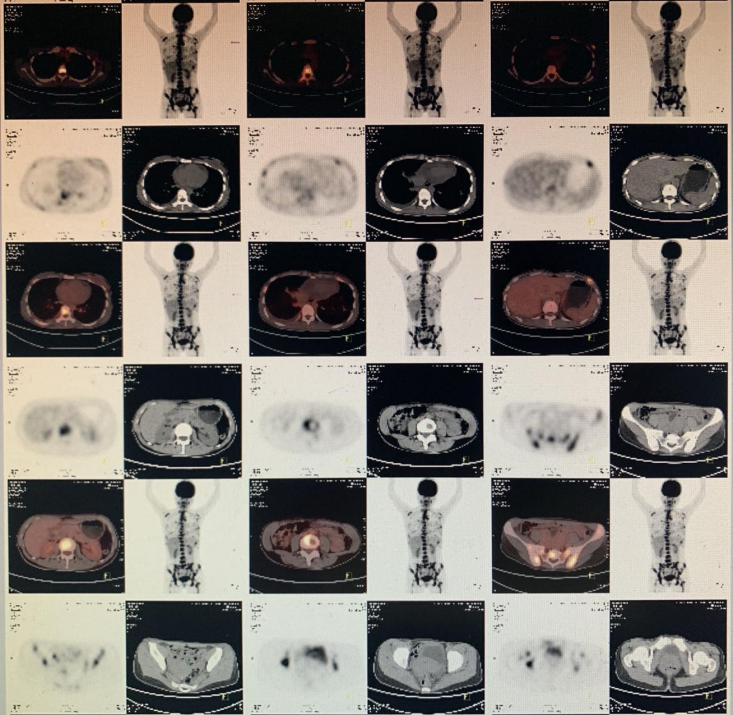

• PET-CT:1.左乳多个代谢增高结节,倾向乳腺癌(多灶);2.左腋窝多个代谢增高淋巴结,倾向肿瘤转移;3.双颈部 IIB 区多个代谢增高淋巴结,肿瘤转移不能除外;4.全身多发骨质破坏代谢增高,多考虑肿瘤转移;5.余未见明确异常征象。

图片

图 5 PET-CT